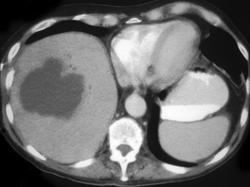

问题 女,35岁,右上腹痛、高热、白细胞计数升高,CT扫描如图,最可能的诊断是 ( )

选项 A、肝淋巴瘤 B、肝胆管细胞癌 C、肝脓肿 D、肝炎性假瘤 E、肝癌

答案 C